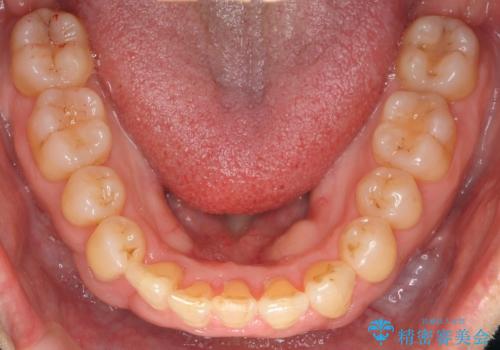

右下の犬歯の1本抜歯で最小限の抜歯で並べることができました。

奥歯も上下交互になるようにかみ合わせることができました。